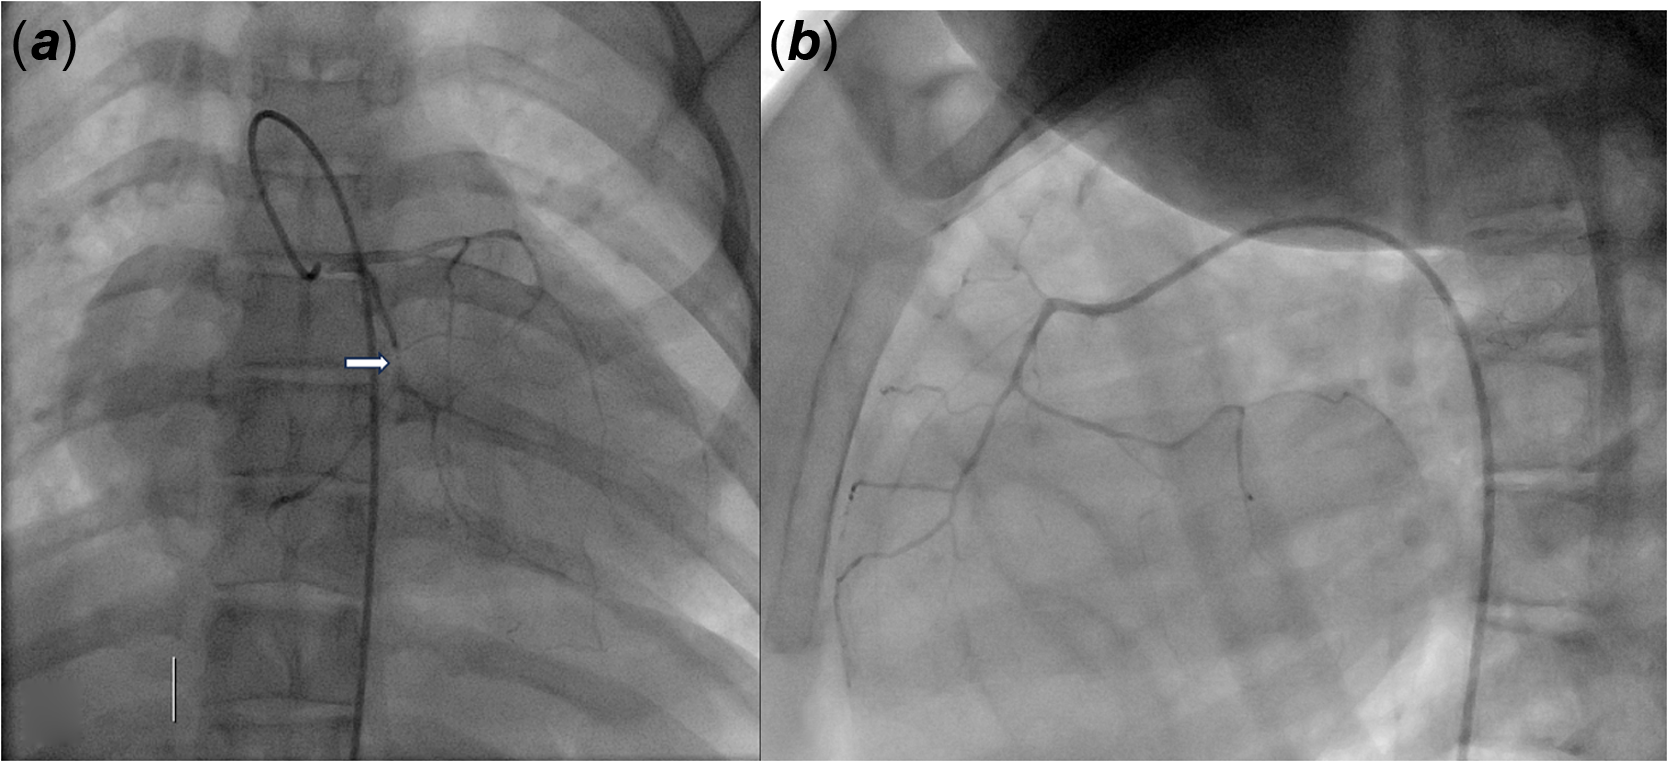

A coronary CT scan revealed subendocardial hypodensity suggestive of ischaemic injury sequelae in the inferolateral territory. Follow-up laboratory tests showed a troponin increase, reaching a maximum of 7600 ng/L within 12 hours of the initial measurement. Diagnostic coronary angiography revealed tri-branch lesions and highlighted a diminutive left and right coronary network with almost complete stenoses or occlusions staggered along the circumflex artery (Figure 2). There was no indication for interventional treatment due to diffuse atheromatous lesions. Medical management was exclusively initiated, including dual antiplatelet therapy, management of cardiovascular risk factors such as dyslipidemia, and cardioprotective treatment.

Figure 2 Conorary angiography (using a four French catheter) revealing tri-branch lesions. ( a ) Contrast injection in left coronary trunk: tiny left coronary network with almost complete occlusions staggered on the circumflex artery over 2,6 mm (arrow). ( b ) Contrast injection in the right coronary: tiny right coronary network.